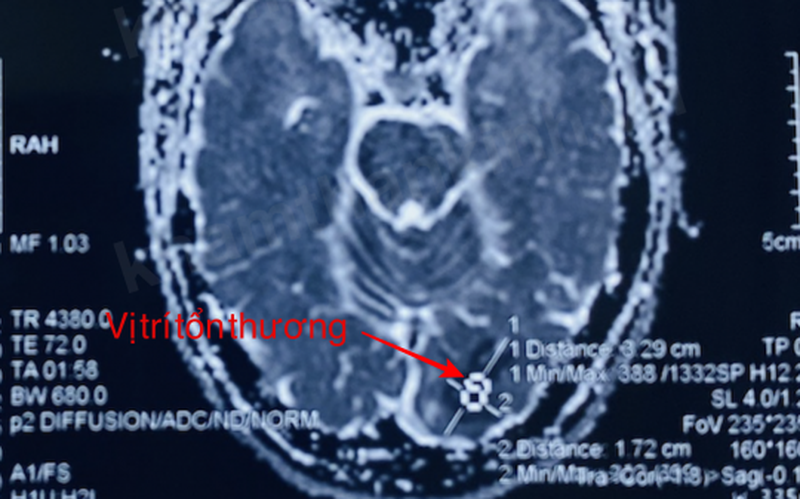

Bệnh nhân được đưa vào Bệnh viện Hữu nghị Việt Tiệp trong tình trạng thị lực mắt phải 8/10, soi đáy mắt và mắt trái bình thường, kết quả chụp cộng hưởng từ sọ não cho thấy hình ảnh nhồi máu não thùy chẩm bên trái.